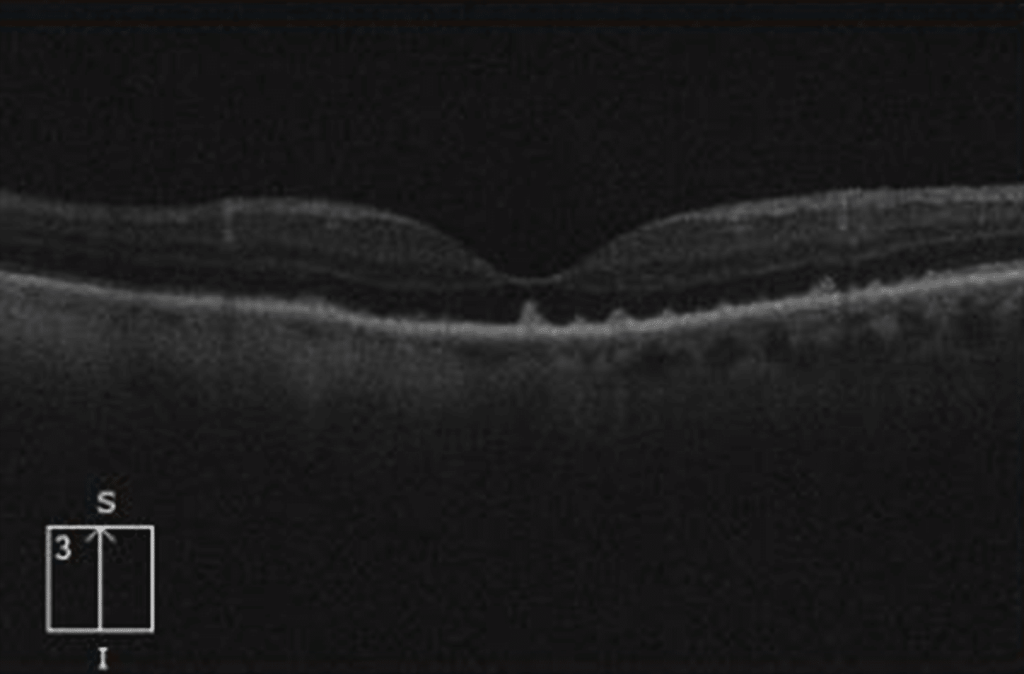

Coroidopatía placoide sifilítica aguda

Esta entidad se caracteriza por una lesión hipopigmentada macular (bilateral o unilateral) relativamente tenue. Si observamos el fondo de ojo con mucho aumento, esta lesión puede pasar desapercibida.

En el OCT típicamente veremos proyecciones en forma de «dedo» desde las capas más externas de la retina hacia capas más internas.